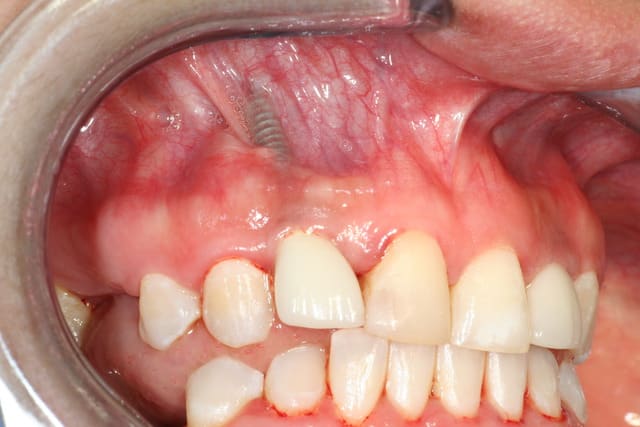

Motif de consultation fistule sur celui de la 22.

Celui de la 12 hors créte on le voit parfaitement par transparence de la gencive (la patiente doit revenir dans 10 jours je ferais des photos, Et elle doit me ramener un scanner de l´année derniere.).

Ma recomandation enlever les 2. Ça va etre sportif de ne pas les casser vu le diametre et la longueur.Faire des gréfes est mettre quelque chose de plus "Classique".

Allez je vous poste une petite photo du cas qui peut aider vu qu´on voit les implants,et qui risque de refroidir ceux qui proposent une aproche conservatrice.

Selon les dires de la patiente il sagirait de la seconde option implanto exclusif trés gros poseur.

L´implant est visible depuis le premier jour. La patiente a demandé,le gars lui a dit que c´etait normal.